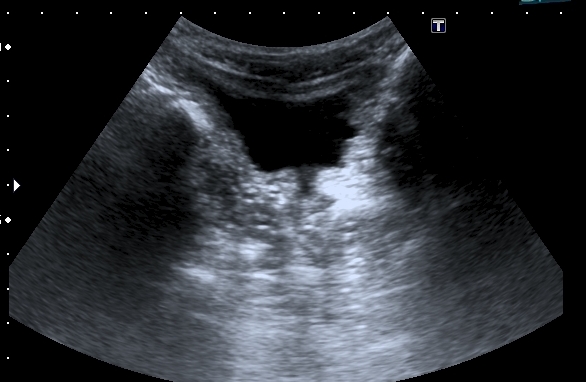

Почки:

Определяется небольшое расширение лоханок обеих почек, стенки их гиперэхогенные, утолщены.

Меня больше всего заинтересовало тканевое образование в нижнем полюсе левой почки - гиперэхогенное, многоузловое. Есть мысли про причину такого состояния почек, но пока хочу выслушать мнения коллег. Буду очень благодарен за отзывы.

Спленомегалии нет. печень без признаков фиброза . Почки уменьшены ( правая - 50 х 20 мм, левая - чуть больше , но за счёт образования нижнего полюса). В левой почке в образовании - есть одиночная небольшая киста ( см клип про почки №3), но на поликистоз непохоже. Ещё одно "но" : с аутосомно - рецессивной поликистозной болезнью почек до 10 лет не живут.

Еще раз пересмотрел клипы. У меня есть впечатление, что подрасширены ЧЛС почек - так ли это? - на этом факте основывается предположение о возможной рефлюкс-нефропатии. Если такого впечатления нет,то нужно вернуться к варианту АРПКБ почек. Что касается продолжительности жизни у больных с АРПКБ почек, то все зависит от того сколько процентов клубочков поражено и насколько поражена печень.